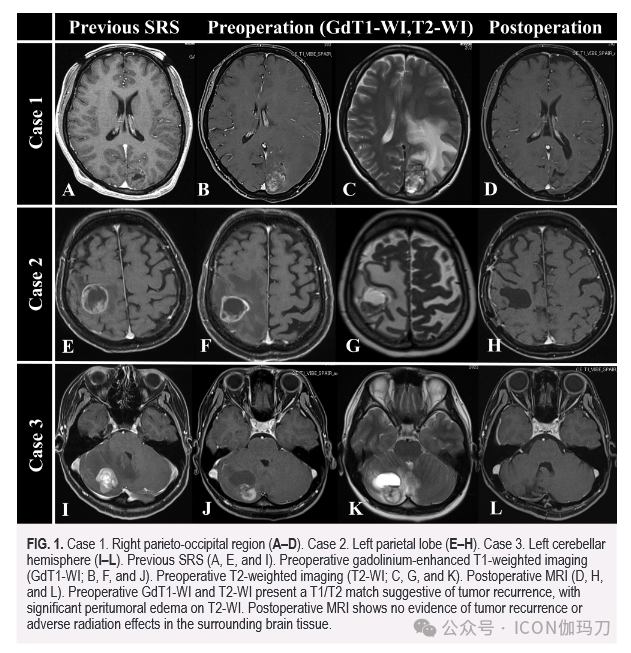

1.病例1。右顶枕区(A-D)。病例2。左顶叶(E-H)。病例3。左小脑半球(I-L)。术前SRS 治疗(A、E、I)。术前钆剂增强T1加权成像(GdT1-WI;B, F, J).术前T2加权成像(T2-WI;C、G、K)。术后MRI (D、H、L)。术前GdT1-WI和T2- wi呈T1/T2匹配提示肿瘤复发,T2- WI显示肿瘤周围明显水肿。术后MRI未见肿瘤复发或周围脑组织放射副反应。

病例1。一名42岁的女性最初被诊断为肺腺癌脑转移。在就诊时,她有多个小的无症状病变,所有这些病变都接受了SRS治疗(边缘剂量为20 Gy)。治疗16个月后,随访影像学显示枕部病变再生;然而,患者仍然无症状。鉴于无症状,选择SRS再程照射(边缘剂量为18 Gy)而不是切除(图1A)。然而,在第二次SRS治疗后15个月,患者出现了明显的神经系统症状,包括右侧视野缺损、Gerstmann综合征和右侧上肢轻瘫。MRI显示肿瘤进展伴广泛的瘤周水肿(图1B和1C), T1/T2匹配提示肿瘤复发而非放射性坏死。基于此评估,术前重复SRS使用16 Gy的边缘剂量,然后在第二天进行大体全切除。随访35个月后,患者无复发(图1D)。

一位65岁的女性,诊断为子宫内膜癌脑转移,表现为轻微的右侧感觉障碍。由于病变面积大且靠近运动皮层,因此采用分次立体定向放射治疗(FSRT)(边缘剂量为35 Gy,分5次)。肿瘤最初反应良好,病变缩小,症状改善。然而,7个月后,患者出现左侧偏瘫,左侧感觉丧失恶化。虽然肿瘤大小比最初表现时略小,但MRI显示肿瘤囊性成分增大,瘤周水肿加重(图1F和G)。患者术前接受边缘剂量为18 Gy的重复SRS治疗后行切除。虽然患者术后20个月因原发肿瘤进展而死亡,但没有脑转移瘤的证据(图1H)。

一位41岁的女性被诊断为无症状的小脑乳腺癌转移瘤。患者接受FSRT治疗(边缘剂量为35 Gy,分5次),肿瘤缩小。然而,26个月后,患者出现严重的共济失调,MRI显示肿瘤囊性增大,伴瘤周水肿(图1J和K)。鉴于症状进展明显,且T1/T2匹配指征明显,术前以18 Gy的边缘剂量靶向增强成分进行重复SRS,然后切除。随访19个月后,患者无复发(图1L)。